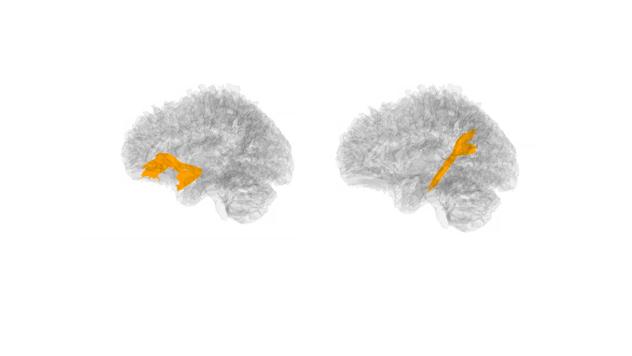

More prenatal sleep problems across pregnancy were associated with higher neonatal FA in the uncinate fasciculus (left: b = 0.20, p = .004; right: b = 0.15, p = .027). Higher neonatal uncinate FA was linked to infant negative emotionality, and uncinate FA partially mediated the association between prenatal maternal sleep and behavioural observation of infant negative emotionality.

结果

妊娠期间更多的产前睡眠问题与钩束 FA 升高相关(左侧:b=0.20,p=0.004;右侧:b=0.15,p=0.027)。较高的新生儿钩束 FA 与婴儿负性情绪有关,钩束 FA 部分介导了产前孕妇睡眠与婴儿行为观察负性情绪之间的关联。